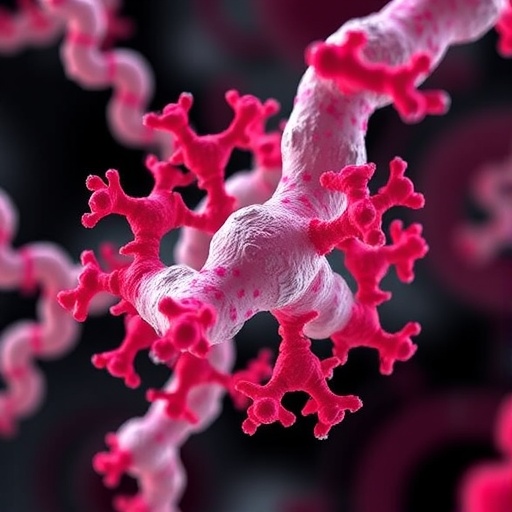

The UMSOM team, led by Dr. Mark T. Gladwin and Dr. Jason J. Rose, focused on a bioengineered solution inspired by a natural bacterial protein known as RcoM, a regulator of metabolism in Paraburkholderia xenovorans. This protein naturally senses trace carbon monoxide, allowing the bacteria to respond to environmental CO levels. Harnessing this biological specificity, the researchers created an enhanced version dubbed RcoM-HBD-CCC, engineered to act as a molecular sponge that binds CO in the bloodstream with remarkable selectivity and minimal interaction with oxygen or other critical molecules.

Mechanistically, carbon monoxide’s toxicity arises from its binding to hemoglobin’s heme iron centers, forming carboxyhemoglobin, which is incapable of oxygen transport. By introducing a high-affinity hemoprotein that preferentially steels CO molecules away from hemoglobin, RcoM-HBD-CCC effectively re-establishes oxygen delivery pathways at the molecular level. This direct removal strategy contrasts with oxygen therapies that merely push the equilibrium toward dissociation but do not actively scavenge CO.

The development of RcoM-HBD-CCC aligns with a broader trend in biomedical engineering: the repurposing and refinement of natural proteins to meet therapeutic challenges. By starting with a naturally evolved, CO-sensing protein and employing sophisticated protein engineering techniques to optimize its binding characteristics and pharmacokinetics, the researchers have exemplified a model of precision bioengineering that balances efficacy with safety.